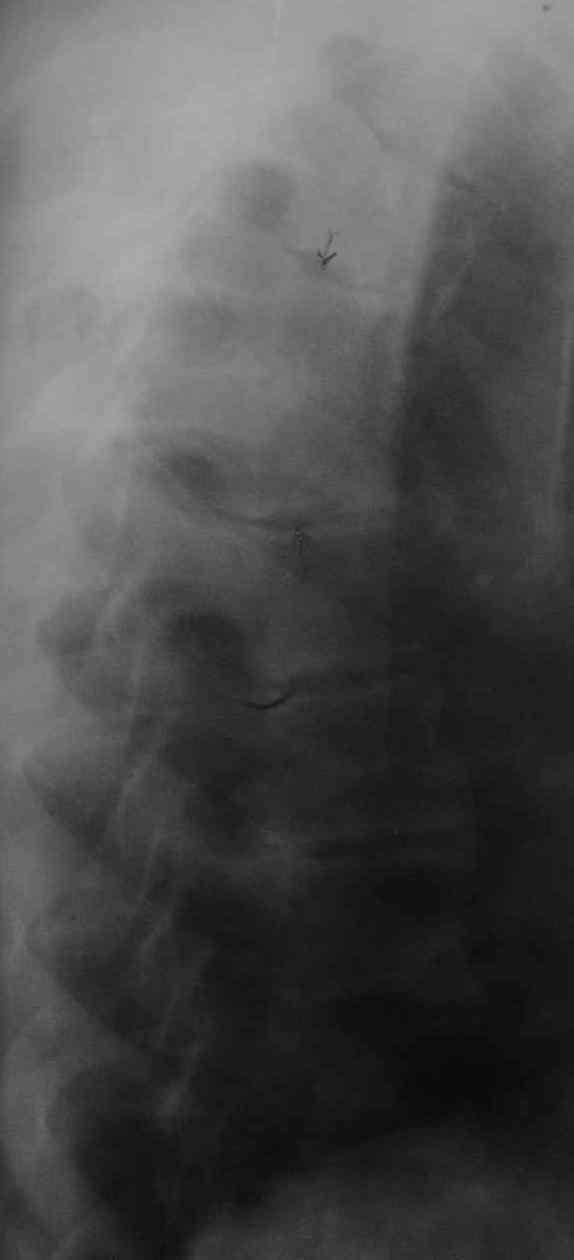

1. Rо-графия грудного и поясничного отделов позвоночника - деструкция с клиновидной деформацией Th5-6. Закл.: застарелый компрессионный перелом? Мт?

21 марта больной скончался. На вскрытии - внутренние органы без признаков какой-либо патологии. При разведении волокон передней продольной связки в проекции Th4-6 была вскрыта гнойная полость с наличием деструкции тел указанных позвонков, с прорывом гнойника в позвоночный канал. Дуги и отростки позвонков - без признаков поражения. Гной сливкообразной консистенции, зеленоватого цвета. Гнойных затеков в мягких тканях также не обнаружено. Таким образом, выставлен п\а диагноз: гнойный остеомиелит тел Th4-6 c прорывом в позвоночный канал.